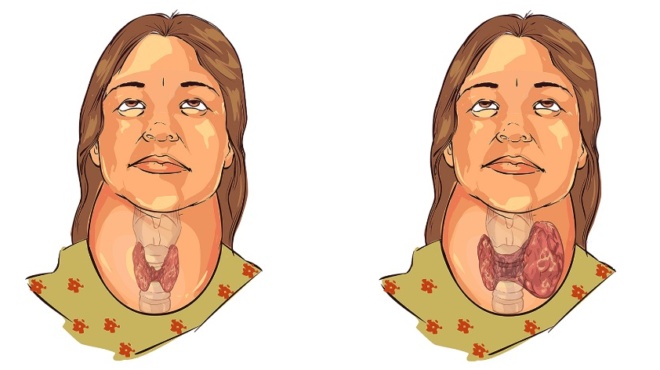

Αγγειίτιδα: Πρόκειται για μια φλεγμονή των αιμοφόρων αγγείων. Δηλαδή, μια πάθηση που προκαλεί αλλαγές στα τοιχώματα των αιμοφόρων αγγείων. Από εκεί και πέρα, οι αλλαγές περιορίζουν τη ροή του αίματος. Μάλιστα, αυτό έχει ως αποτέλεσμα να επέρχεται η σταδιακή καταστροφή των οργάνων, καθώς και των ιστών.

Αγγειίτιδα: Μορφές της νόσου